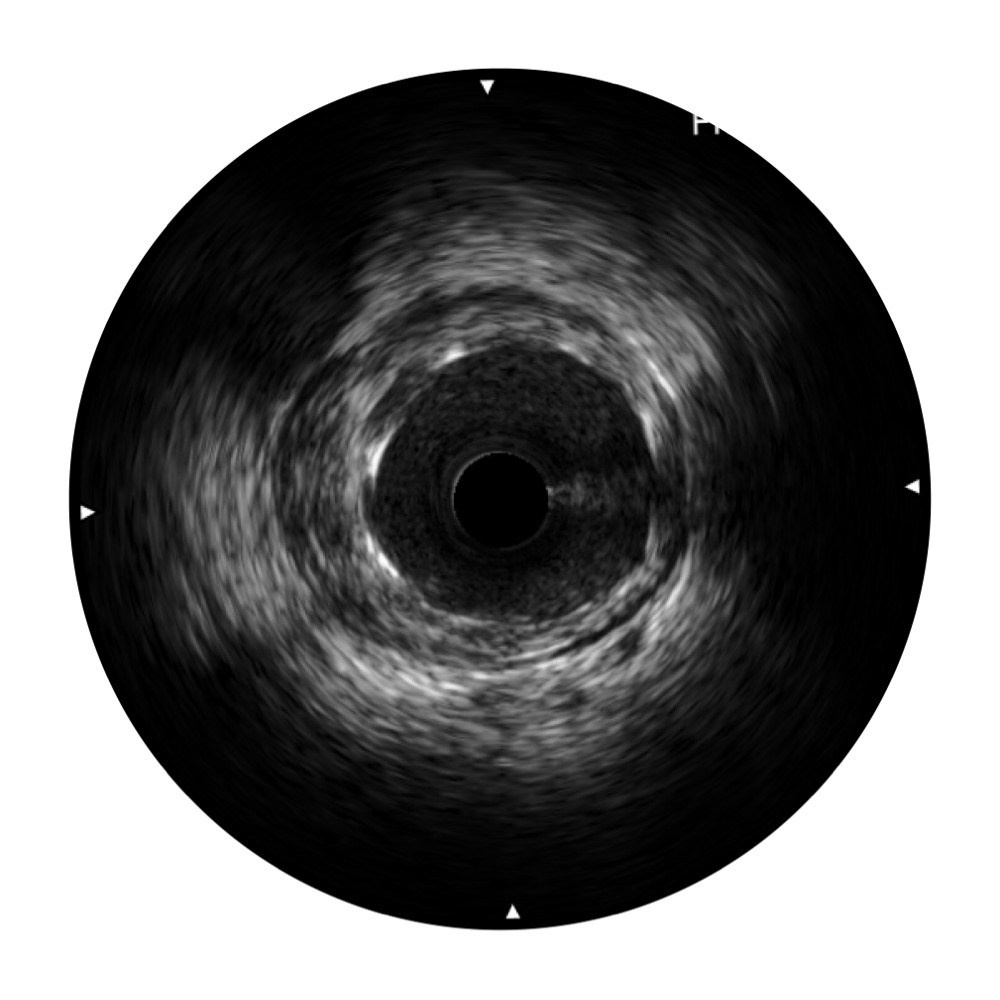

传统IVUS图像

对比传统IVUS导管成像,球速体育入口宽频IVUS图像的近场支架梁显影更细腻,远场中膜外血管仍清晰可辨,兼顾远中近,兼顾分辨力与穿透深度